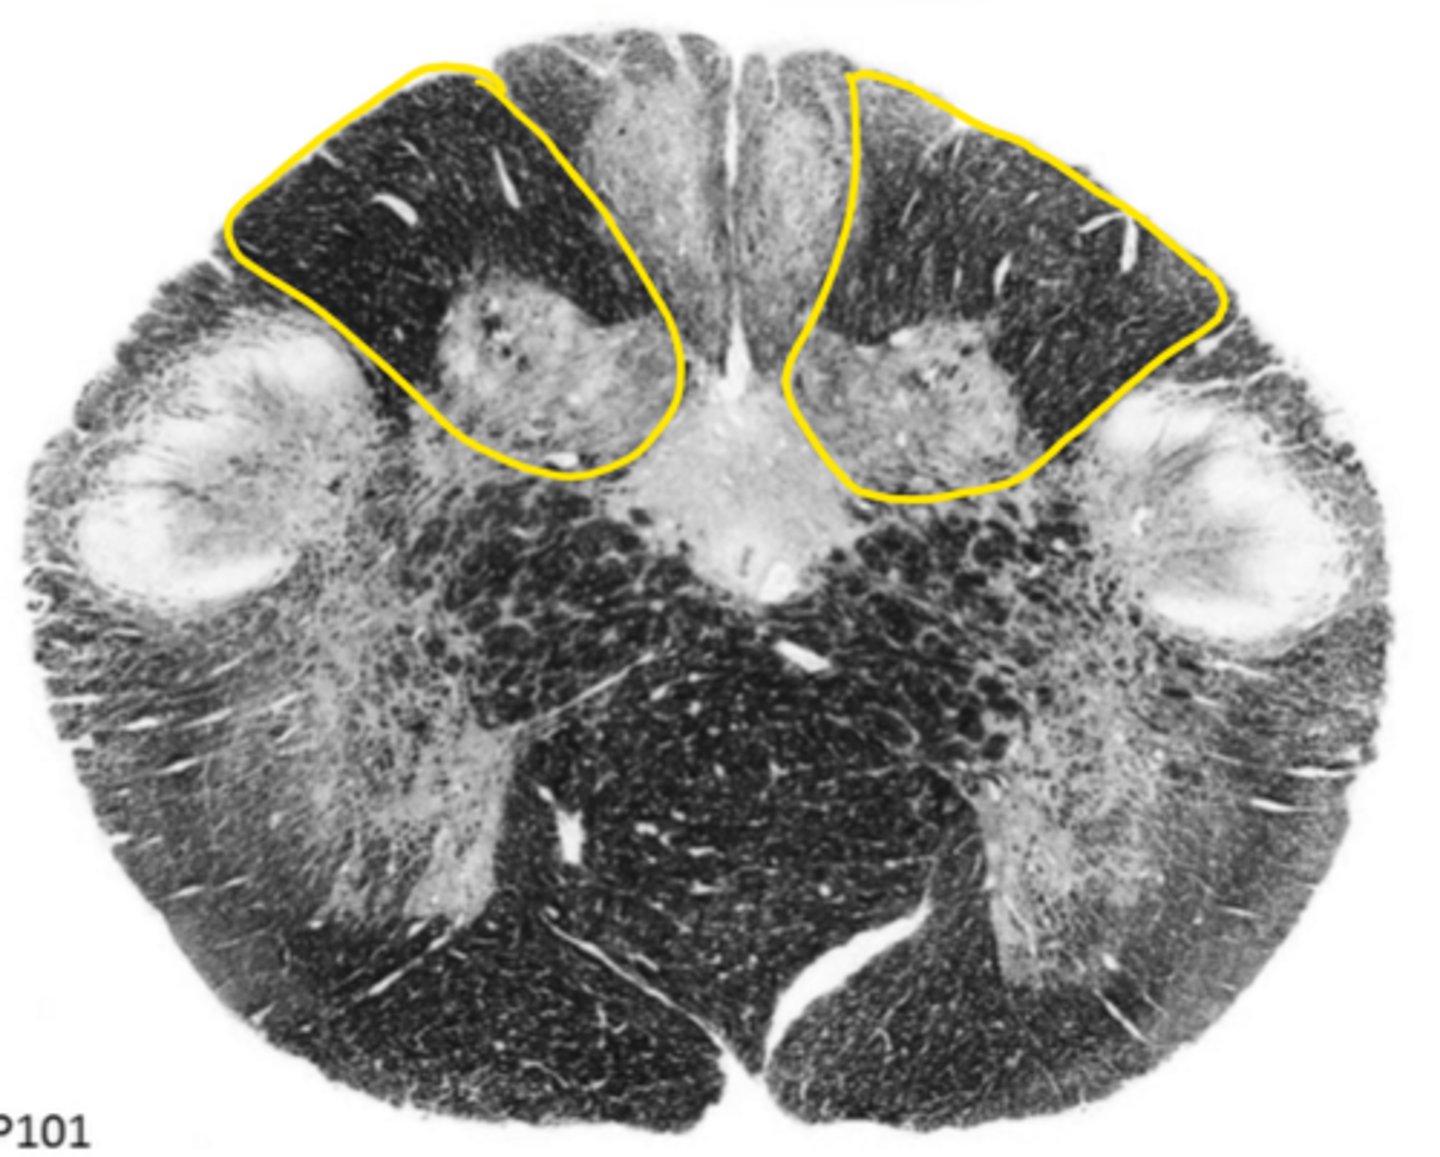

open medulla

ID the brainstem level